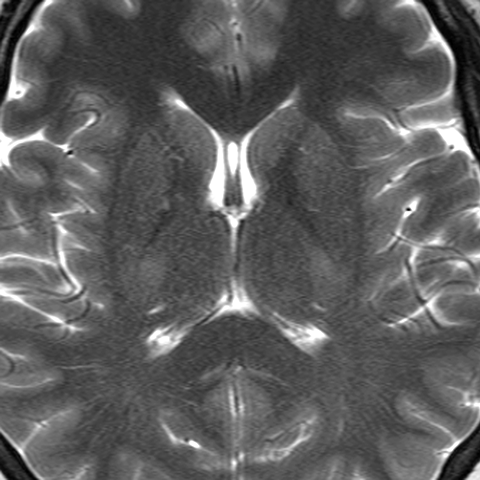

Cerebral Hemispheres, Axial CECT (normal) [6 of 6]